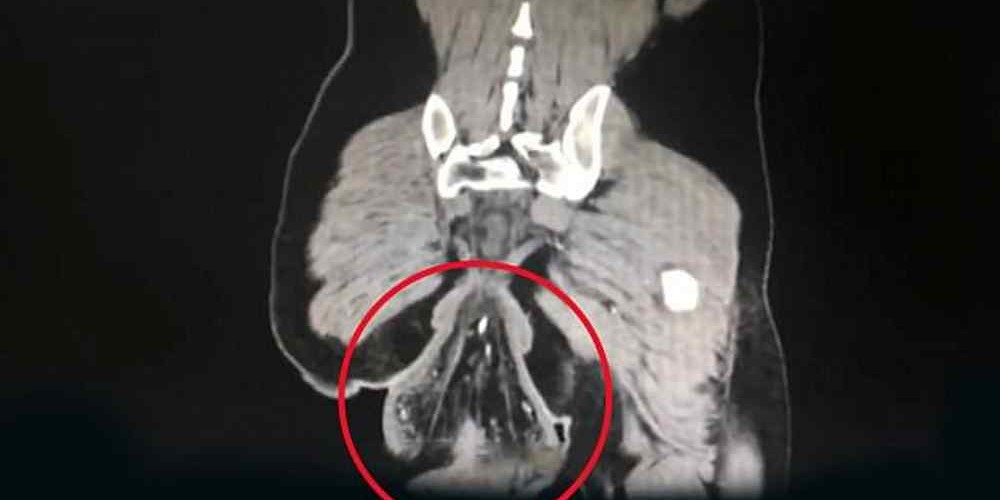

O médico, afirmou que o caso do chinês era grave. Na imagem de uma tomografia é possível ver que o nódulo tinha cerca de 16 centímetros de diâmetro.